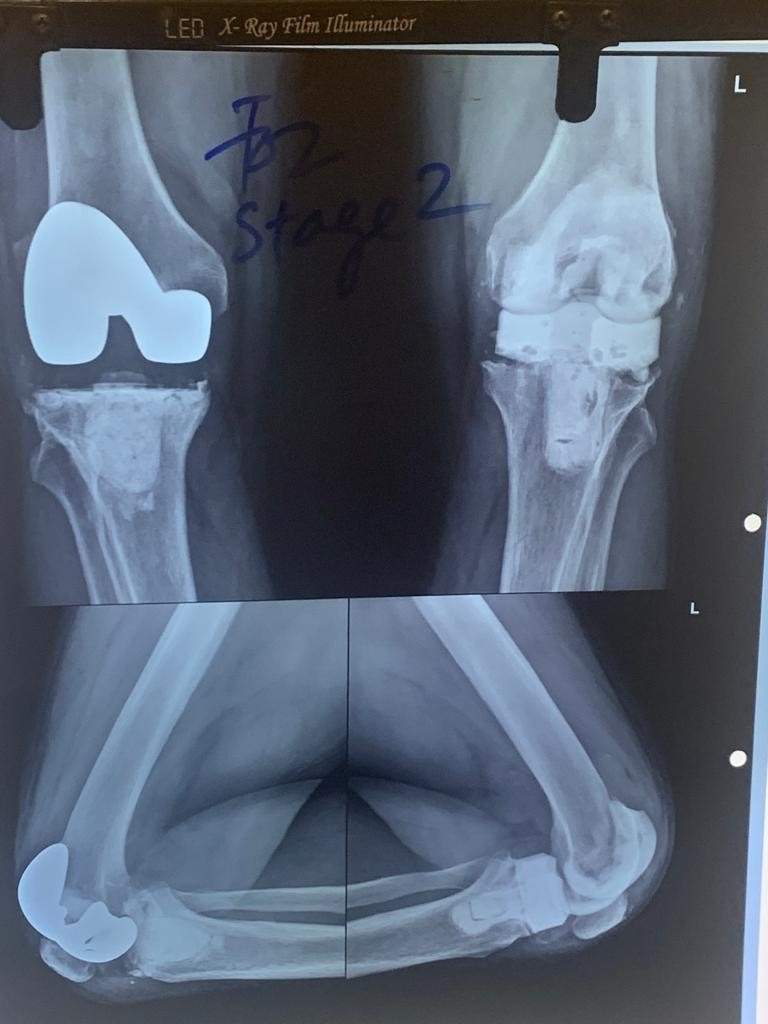

1. Knee Pain Treatment by Orthopedics Surgeon

Multiple reasons can cause knee pain, and athletes suffer from such pain due to injury. On the other hand, people over 60 years of age may become knee pain victims due to the body’s scarcity of calcium and other crucial minerals. The best way of dealing with knee pain is to meet an orthopedic specialist at the earliest.

The orthopedic doctor in Gurgaon may recommend a few tests. After checking the test results, the doctor will suggest treatments when the disease is diagnosed. In the case of severe damage to the knee, surgery is essential. Therefore, you should find a specialized knee surgeon for knee replacement surgery. Consult Dr Hemant Sharma for Knee Replacement Surgery In Gurgaon